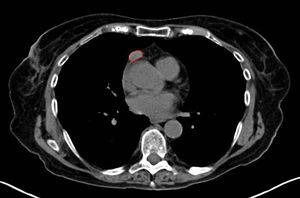

التصوير الطبي

A chest X-ray may identify widening of the mediastinum suggestive of thymoma, but computed tomography (CT) or magnetic resonance imaging (MRI) are more sensitive ways to identify thymomas and are generally done for this reason.[37] MRI of the cranium and orbits may also be performed to exclude compressive and inflammatory lesions of the cranial nerves and ocular muscles.[38]

As thymomas are seen in 10% of all people with the MG, people are often given a chest X-ray and CT scan to evaluate their need for surgical removal of their thymus and any cancerous tissue that may be present.[17][36] Even if surgery is performed to remove a thymoma, it generally does not lead to the remission of MG.[48] Surgery in the case of MG involves the removal of the thymus, although in 2013 there was no clear indication of any benefit except in the presence of a thymoma.[52] A 2016 randomized controlled trial, however, found some benefits.[53]